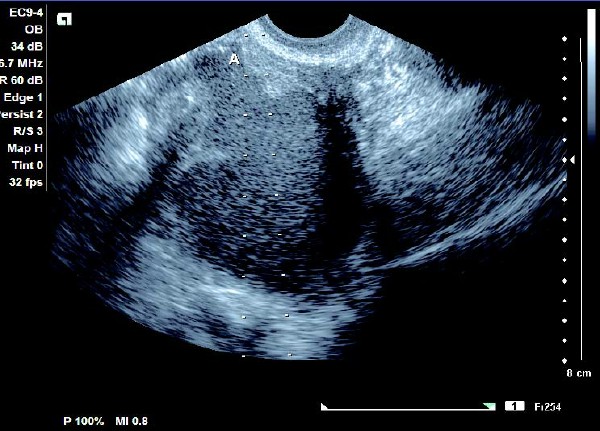

患者,女,35岁。每次月经量少,痛经,近来行经期延长、疼痛加重来院诊治。超声报告显示子宫前倾位,子宫体大小为:5.9cm×5.1cm×4.8cm,形态规则,边界清晰,宫避回声匀称,宫腔线居中,内膜厚度0.6cm,宫内未见异常回声。右侧卵巢内可见大小约5.2 cm×4.9cm的无回声区暗区,壁厚,内壁欠光滑,内见密集细光点,边界清晰。CDFI探测囊壁及囊腔内无血流信号。

超声提示:右侧卵巢巧克力囊肿